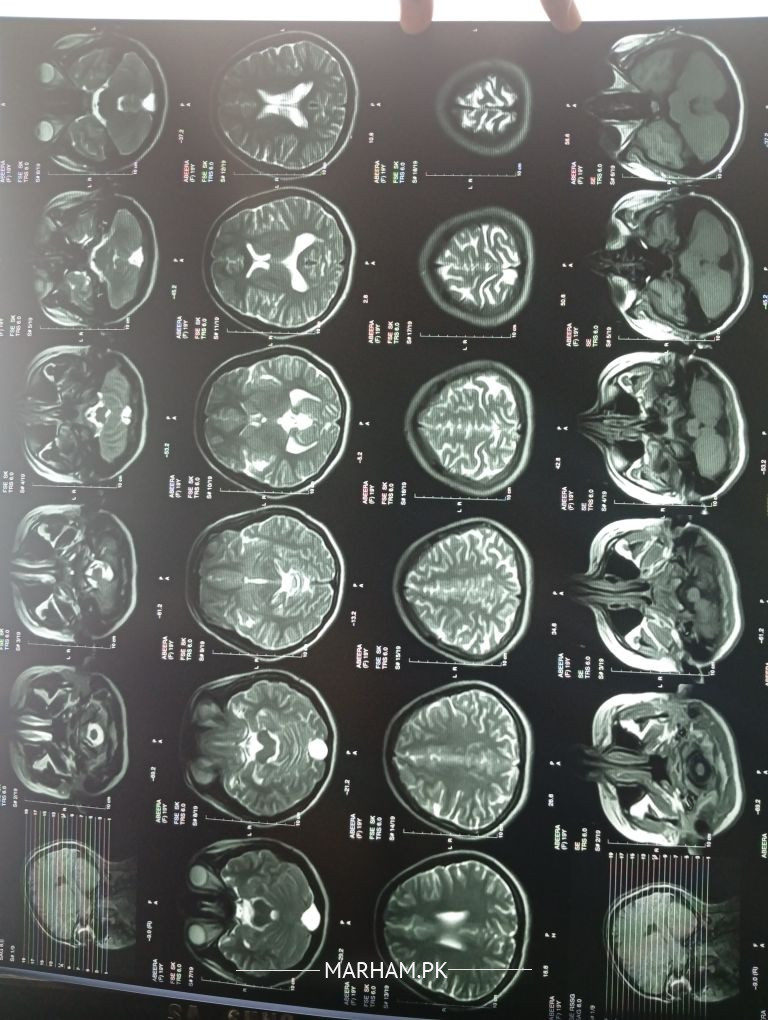

The MRI at first glance appears normal, though the report is awaited.

Need more information about the headache before can guide further.